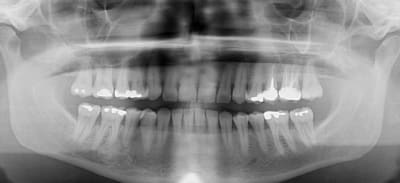

Je soumets à vos avis cette lésion en regard de 45 46 découverte fortuitement à la pano,

Aucune doléance de la part du patient,

Quelle diagnostic ? Quelle conduite à tenir ?

Je pencherais pour un cémentome avec une simple surveillance, est ce que les pros de la patho peuvent me donner leur avis ?

vitalité ???

je ne me priverais pas d'un scan

Je n'ai pas fait de test de vitalité...